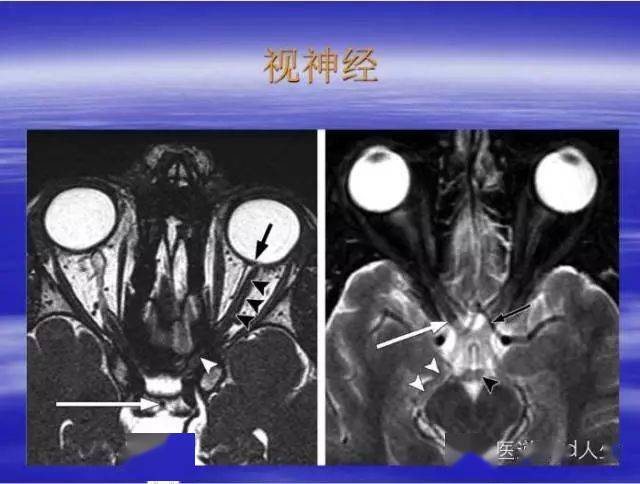

▎视神经病灶